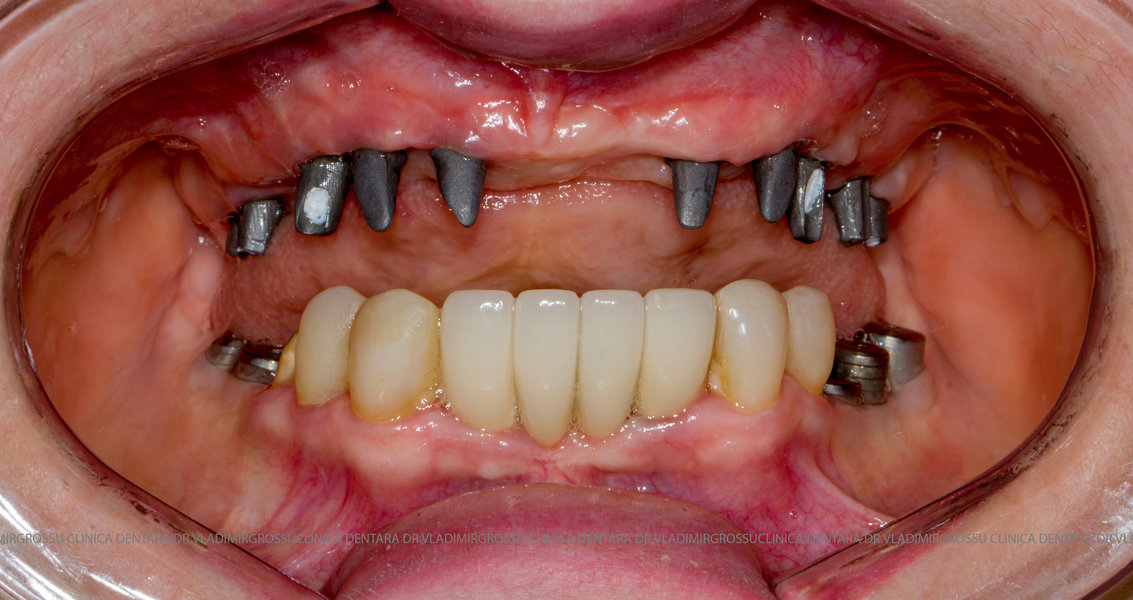

Cazuri clinice conceptul All-on-6